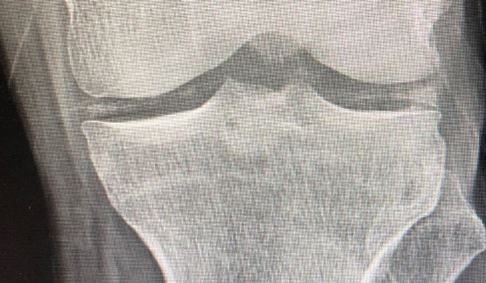

The man in his early 70s complains of leg pain lasting a month and of arm pain that came on about 1 week ago. Does the x-ray offer a clue to a diagnosis?

History of present illness. A man in his early seventies presents to the hospital with 1 month of left leg pain and 1 week of left arm pain. He has a history of high cholesterol, hypertension, and diabetes. He states that the arm hurts from his shoulder all the way down to his hand and the entire left leg hurts as well, but not as bad as the arm. If he had to say which areas hurt the most it would be his left wrist followed by his left knee. He is unsure if there is weakness because the pain is so severe, but he denies any numbness, injury, fever, chest pain, shortness of breath, or other complaints.

Vital signs & physical examination. Vital signs are normal. The physical exam is otherwise normal except for swelling and redness to the left wrist and a possible small effusion of the left knee without any erythema. No induration is noted at either site.

Imaging: X-ray, below